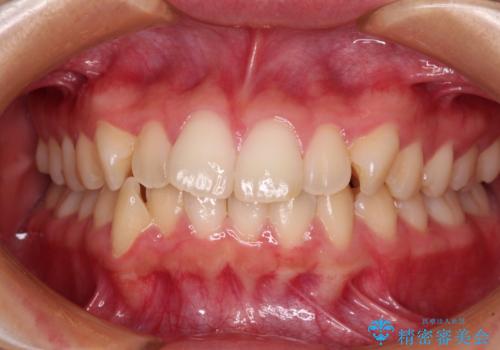

【モニター】処置歯の多い歯列 インビザラインでデコボコを整える